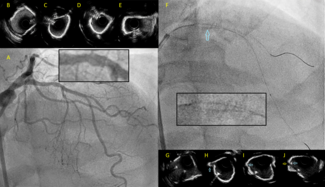

An 83-year-old woman with symptomatic severe aortic stenosis was referred for transcatheter aortic valve replacement. Diagnostic left heart catheterization documented diffuse 3-vessel coronary artery disease.